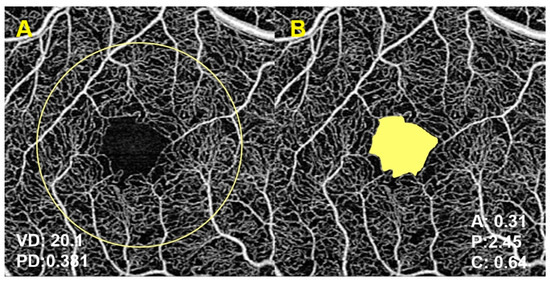

| Vessel density | Mean (SD) | 20.5 (1.9) | 19.9 (1.8) | 19.5 (1.9) | 0.002 ab | 19.8 (1.9) | 19.5 (1.4) | 0.003 cd | 19.8 (1.9) | 19.5 (1.4) | 0.002 f,g |

| (mm−1) | Median (IQR) | 21 (20; 21.8) | 20.1 (18.8; 21.2) | 19.4 (18.6; 21.1) | 20.1 (18.8; 21.2) | 19.9 (18.6; 20.4) | 20.1 (18.8; 21.2) | 19.9 (18.6; 20.4) | |||

| n | 59 | 263 | 74 | 318 | 20 | 317 | 20 | ||||

| Perfusion density | Mean (SD) | 0.37 (0.03) | 0.36 (0.03) | 0.36 (0.03) | 0.111 | 0.36 (0.03) | 0.36 (0.02) | 0.084 | 0.36 (0.03) | 0.36 (0.02) | 0.062 |

| (0–1) | Median (IQR) | 0.38 (0.36; 0.39) | 0.37 (0.35; 0.38) | 0.37 (0.34; 0.38) | 0.37 (0.35; 0.38) | 0.36 (0.35; 0.38) | 0.37 (0.35; 0.38) | 0.36 (0.35; 0.38) | |||

| n | 59 | 263 | 73 | 317 | 20 | 316 | 20 | ||||

| FAZ area | Mean (SD) | 0.24 (0.08) | 0.24 (0.1) | 0.23 (0.1) | 0.919 | 0.24 (0.1) | 0.25 (0.1) | 0.890 | 0.24 (0.1) | 0.25 (0.1) | 0.972 |

| (mm2) | Median (IQR) | 0.24 (0.19; 0.29) | 0.23 (0.17; 0.31) | 0.23 (0.18; 0.29) | 0.23 (0.17; 0.3) | 0.25 (0.17; 0.33) | 0.23 (0.17; 0.3) | 0.23 (0.17; 0.33) | |||

| n | 53 | 244 | 70 | 296 | 19 | 295 | 19 | ||||

| FAZ perimeter | Mean (SD) | 2.05 (0.44) | 2.1 (0.5) | 2.11 (0.51) | 0.714 | 2.09 (0.5) | 2.26 (0.47) | 0.309 | 2.09 (0.5) | 2.24 (0.48) | 0.442 |

| (mm) | Median (IQR) | 2.09 (1.79; 2.29) | 2.1 (1.77; 2.44) | 2.15 (1.83; 2.44) | 2.11 (1.78; 2.43) | 2.38 (1.95; 2.59) | 2.11 (1.77; 2.43) | 2.09 (1.95; 2.59) | |||

| FAZ circularity | Mean (SD) | 0.67 (0.09) | 0.65 (0.09) | 0.63 (0.08) | 0.040 b | 0.65 (0.09) | 0.60 (0.07) | 0.005 de | 0.65 (0.09) h | 0.60 (0.07) h | 0.005 f |

| (0–1) | Median (IQR) | 0.69 (0.62; 0.73) | 0.67 (0.6; 0.72) | 0.65 (0.58; 0.7) | 0.67 (0.6; 0.71) | 0.61 (0.55; 0.65) | 0.67 (0.6; 0.71) | 0.61 (0.55; 0.65) | |||